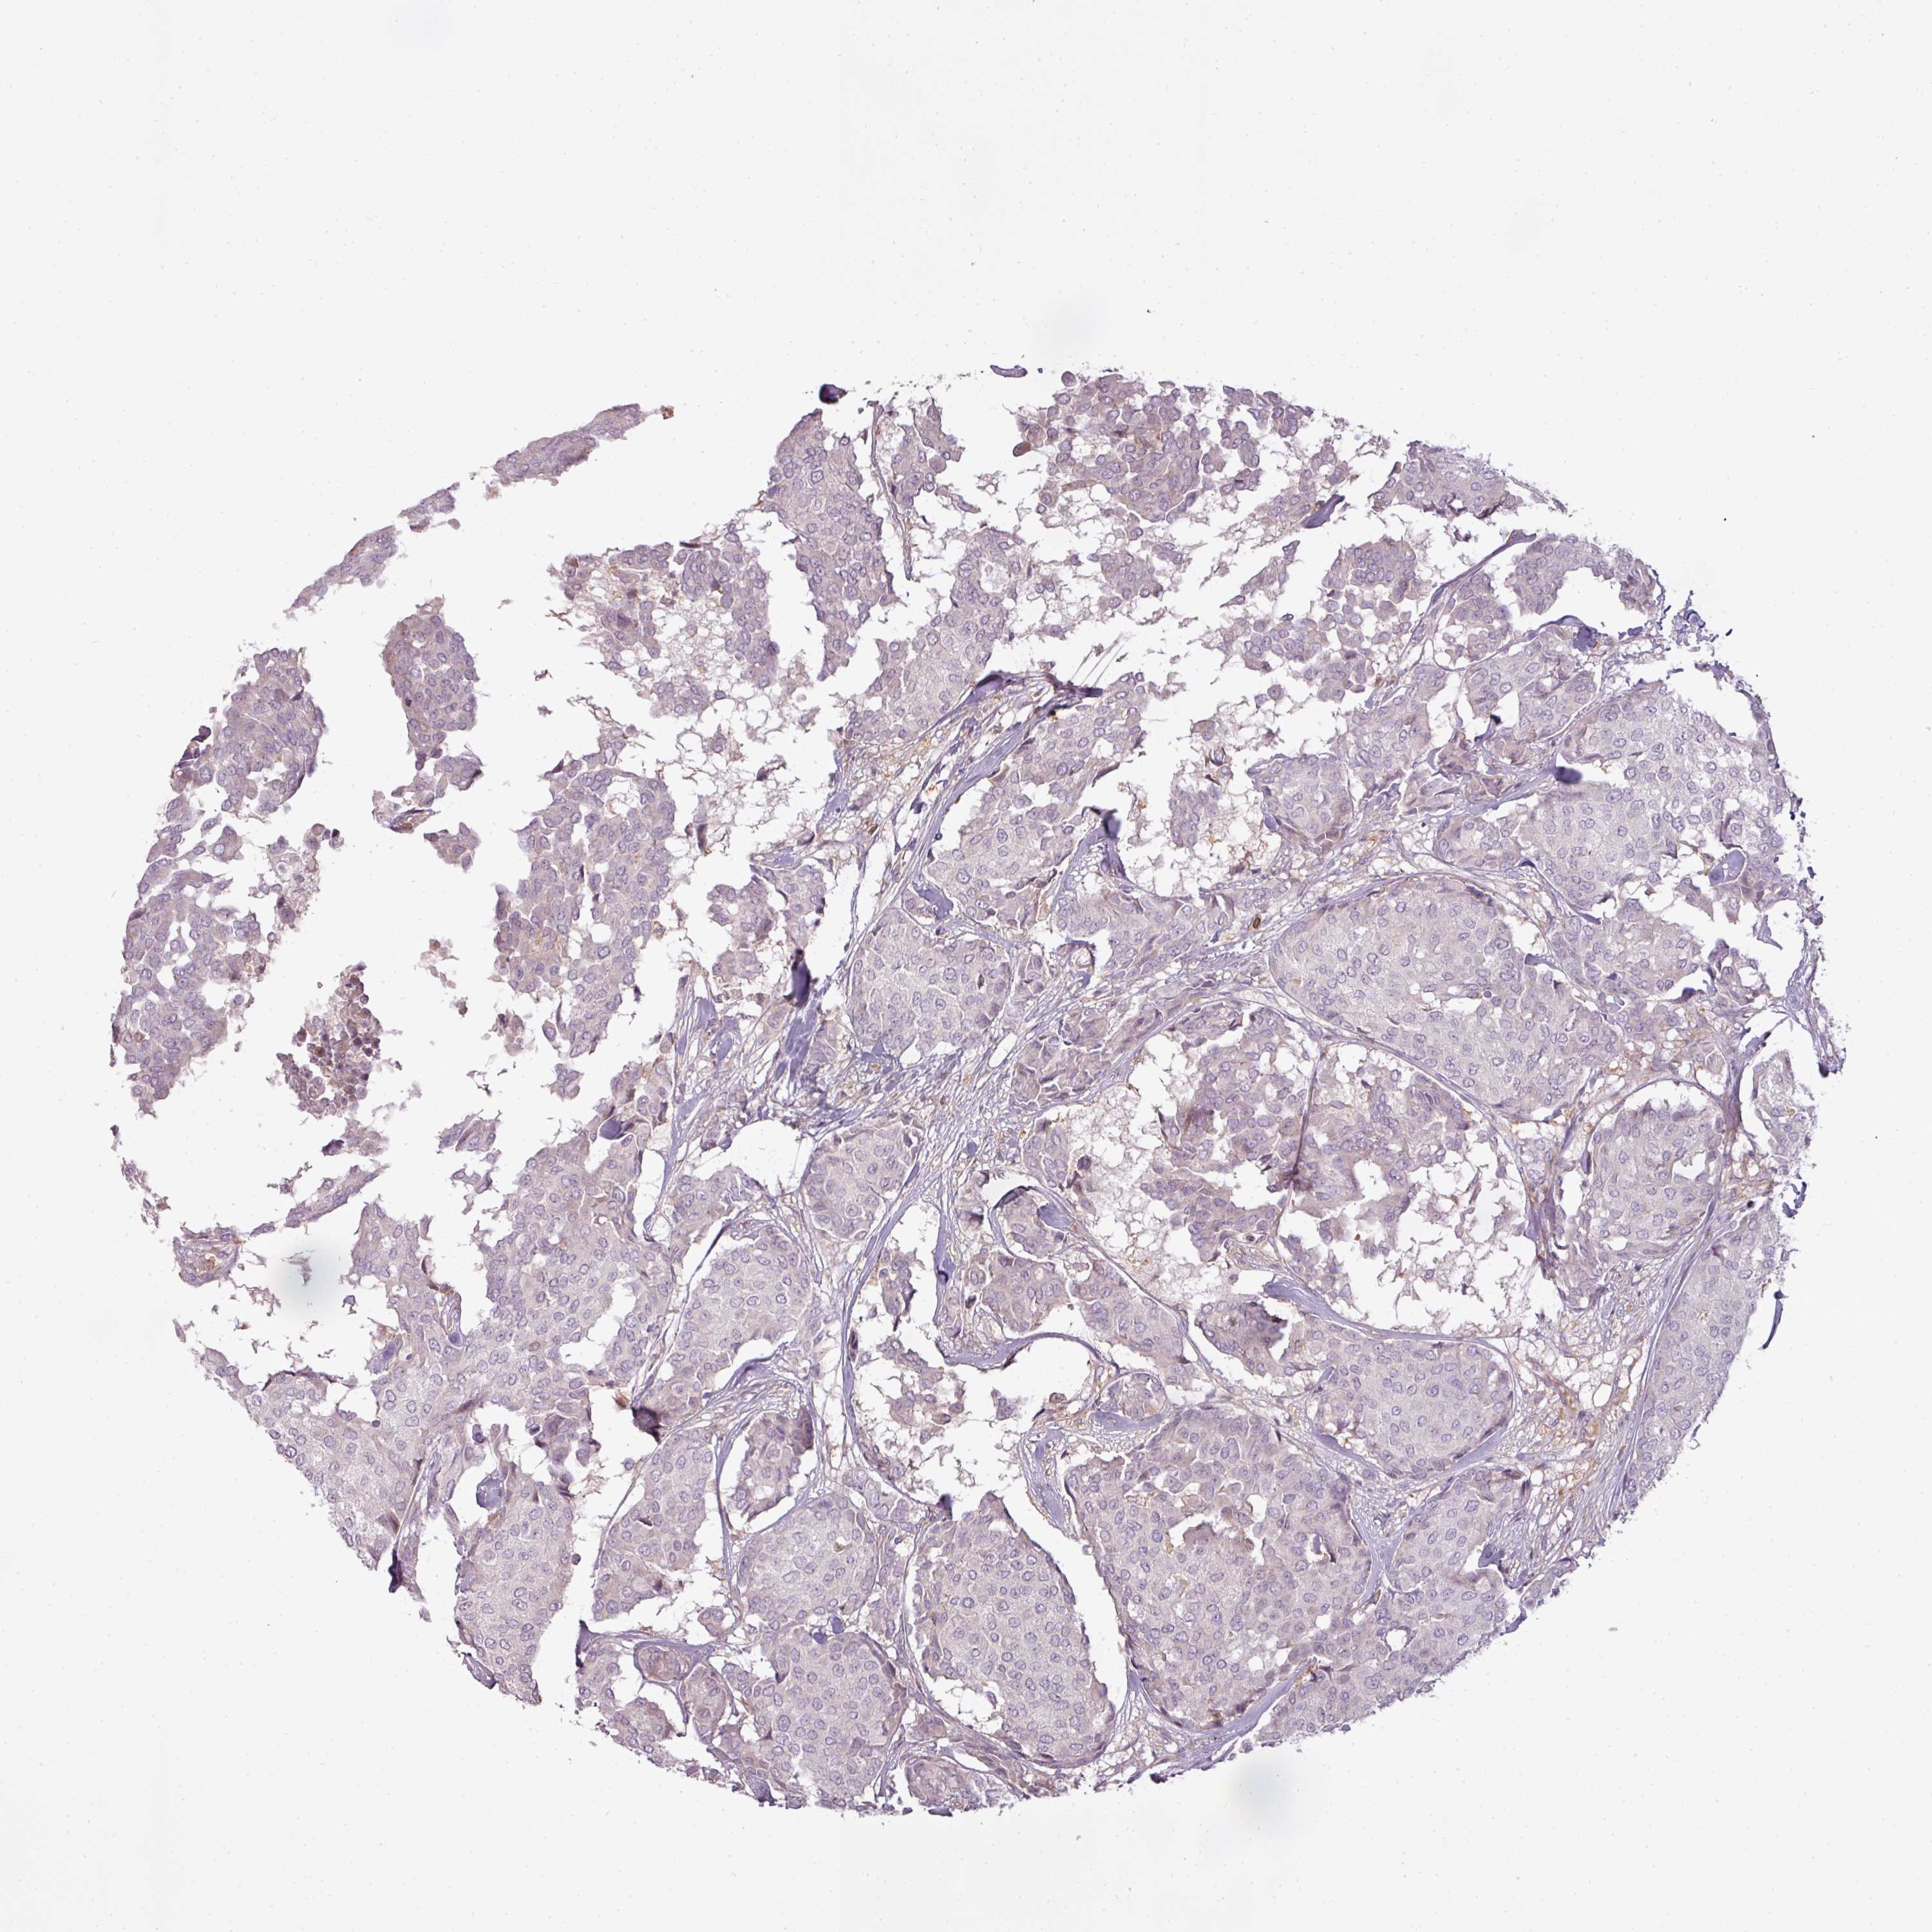

CANCER BREAST CANCER Show tissue menu

Breast cancer

Human cancer